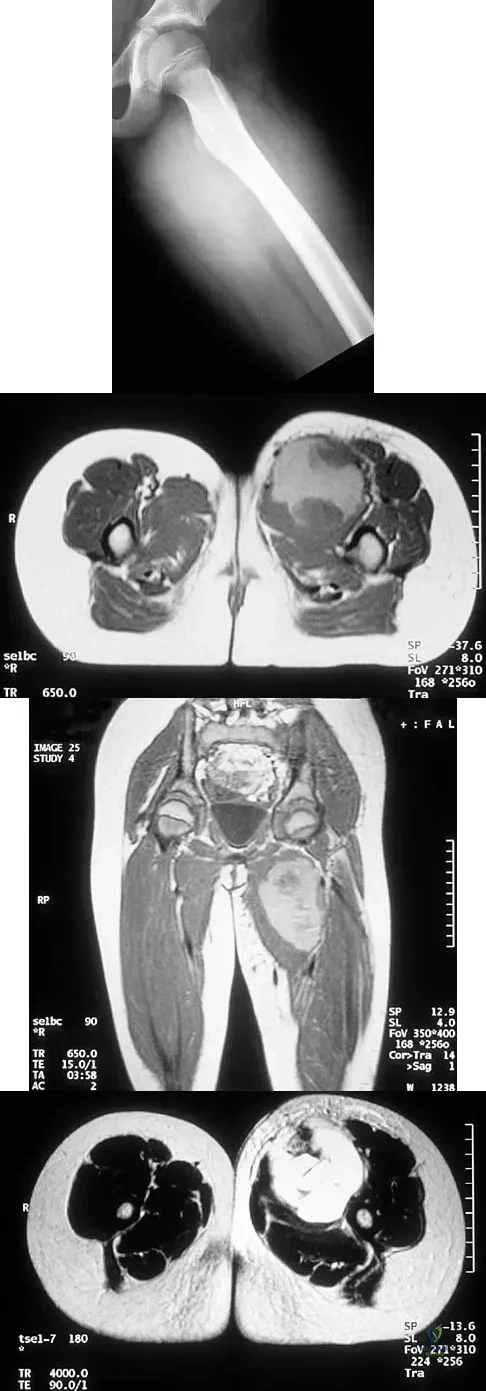

Question 57

An 8-year-old girl has had a painless enlarging mass of insidious onset in the left thigh for the past 3 weeks. Her mother denies any history of trauma, fever, or disease. Examination reveals a nontender, mobile mass in the left medial thigh. Her gait is normal. Figures 25a through 25d show the frog-lateral radiograph, the axial and coronal T1-weighted MRI scans, and the axial T2-weighted MRI scan. Biopsy results reveal a nonrhabdomyosarcoma soft-tissue sarcoma. The most appropriate treatment should consist of

Explanation